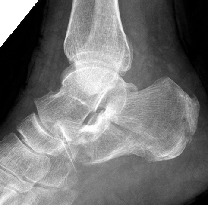

患者术前影像显示根骨粉碎性骨折

常规切开复位内固定术创伤大、复位不准确,存在慢性疼痛、皮肤坏死、足踝活动受限、创伤性关节炎等风险。于是,骨科在中心主任吴超带领下,采用第三代天玑骨科手术机器人为程某开展跟骨微创内固定手术,该手术时间短、透视少、实现了精准复位和螺钉固定;术后影像显示螺钉位置良好,患者关节面恢复。